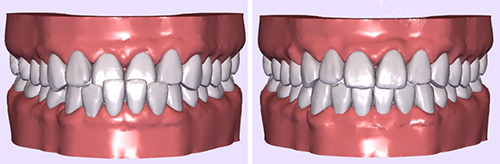

青少年时期是牙齿矫正的黄金期,但面对金属、陶瓷、隐形三种主流牙套,家长和孩子常陷入选择困难。本文结合正畸医生临床经验与患者真实反馈,从美观、舒适度、矫正效率、价格等维度深度解析,帮你找到较适合的方案。

看畸形程度:复杂病例(如骨性错颌)优先金属/陶瓷牙套,轻度畸形可选隐形。